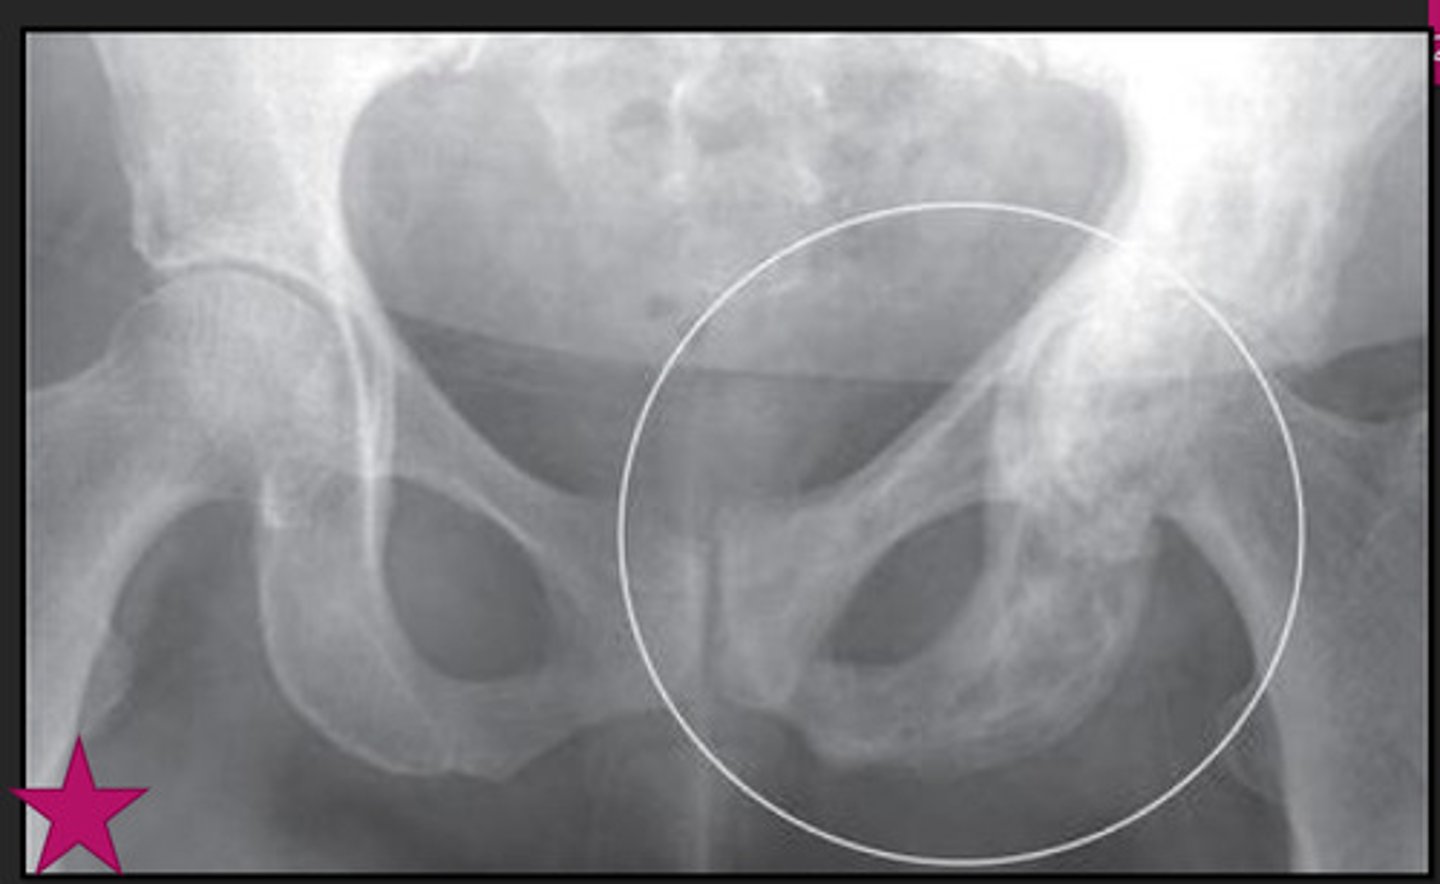

ankylosing spondylitis

young, males

neck/LBP, worse @ night & better w/ exercise

what is ankylosing spondylitis associated w/?

ulcerative colitis

what marker can do patients w/ ankylosing spondylitis test + for?

HLA-B27

hallmark of ankylosing spondylitis

fusion of lumbar spine & sacroiliac joints (sacroilitis)

bamboo spine ("dagger sign" on AP projection)

ankylosing spondylitis; no spaces b/w vertebrae